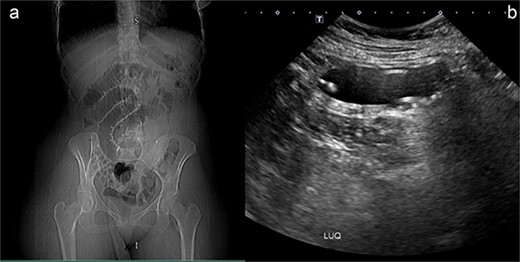

After she arrived in the emergency room, plan X-ray abdomen showed dilated jejunal loops and an ultrasound (US) of her abdomen was carried out, and it was discovered that the gastric balloon in the left upper quadrant of the stomach lumen had drastically shrunk, indicating that it may have ruptured (Fig. 1). Nevertheless, the balloon was not visible during the upper endoscopy that she had later.

(a) Plan X-ray abdomen showing dilated jejunal loops. (b) Abdominal US showing small bowel containing IGB.